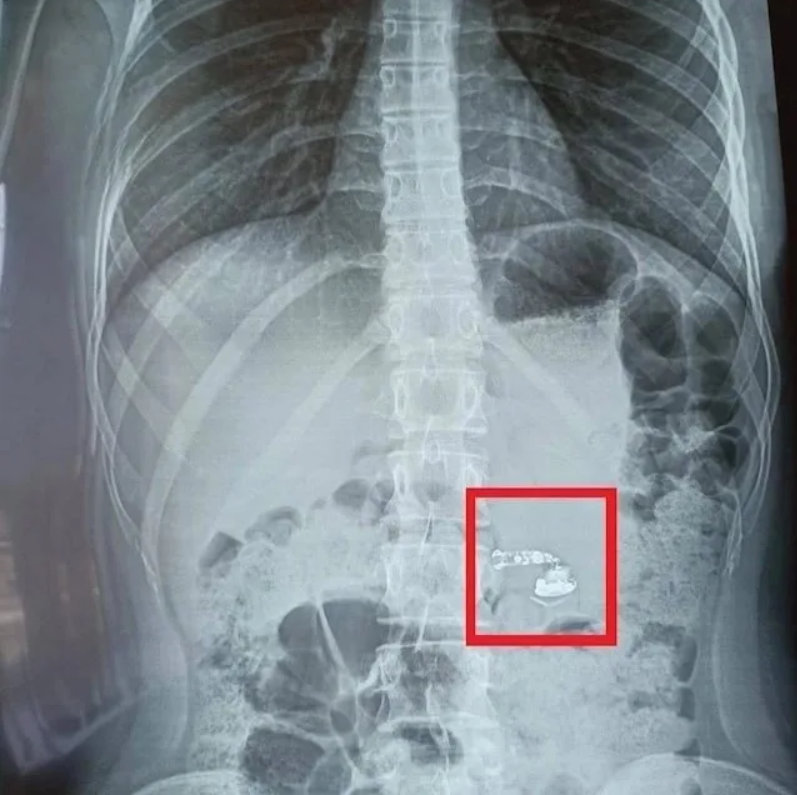

Небольшие кусочки стекла, размером со спичечную головку и без острых углов, обычно не представляют серьезной опасности. Однако, сложно точно определить форму проглоченного осколка. Поэтому, лучше обратиться к врачу. Он оценит ситуацию и определит, какие обследования необходимы.

Если УЗИ или рентген не обнаруживают мелкое стекло, врач может назначить компьютерную томографию (КТ) или магнитно-резонансную томографию (МРТ). После этого, возможно, потребуется наблюдение в течение суток-двух, пока инородный предмет не покинет организм.